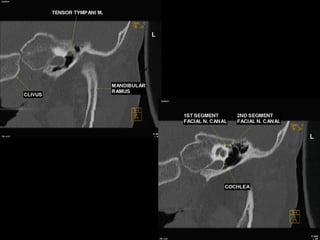

Coronal temporomandibular joint level

 The horizontal carotid canal is seen as an

oval structure just

lateral to petrooccipital suture.

 The semicanal for the tensor tympani

muscle is seen as a small

lucency lateral to the carotid canal.

 The air-filled eustachian tube is inferior to

the tensor tympani,

and the TMJ is seen laterally

Geniculate ganglion level

 Tensor tympani muscle is seen

along the medial wall of the middle

ear, with the cochleariform process

separating it from the eustachian

tube below.

 The anteriormost part of the

cochlea is medial to the tensor

tympani.

 The geniculate ganglion is seen

as a small lucency superior to the

cochlea